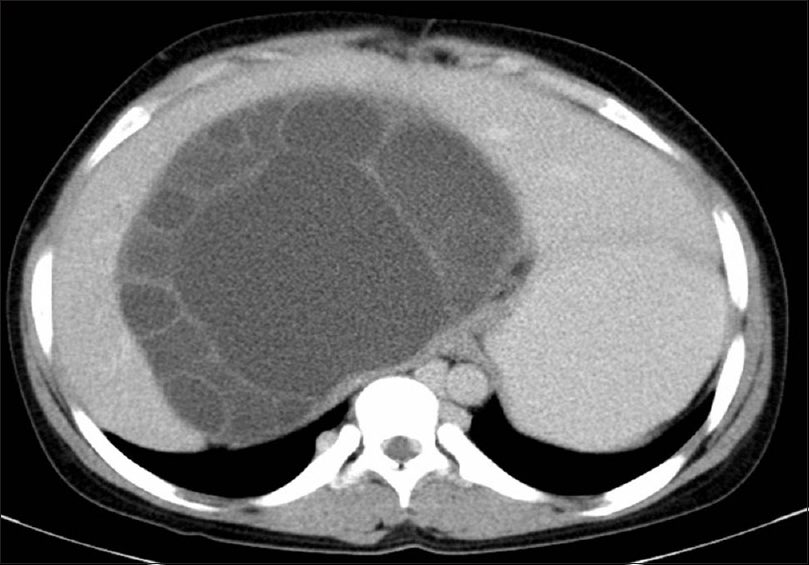

ما تراه هي الاكياس ل

داء المُشْوِكات أو داء المكورات المشوكة (باللاتينية: echinococcosis)أو مرض الأكياس المائية أو الكيس العدري هو مرض يسببه طفيلي من جنس المشوكة يدخل جسم الإنسان عن طريق الفم

✅الجديد هو استئصال كامل الأكياس بكل الأغشية بواسطة “المنظار”تترواح أحجامها من١٨-١٥ سم

يتم تشخيص المرض عن طريق التصوير المقطعي أو الاشعه الصويتيه (توضح الصور وجود الأغشية الطفيلية).